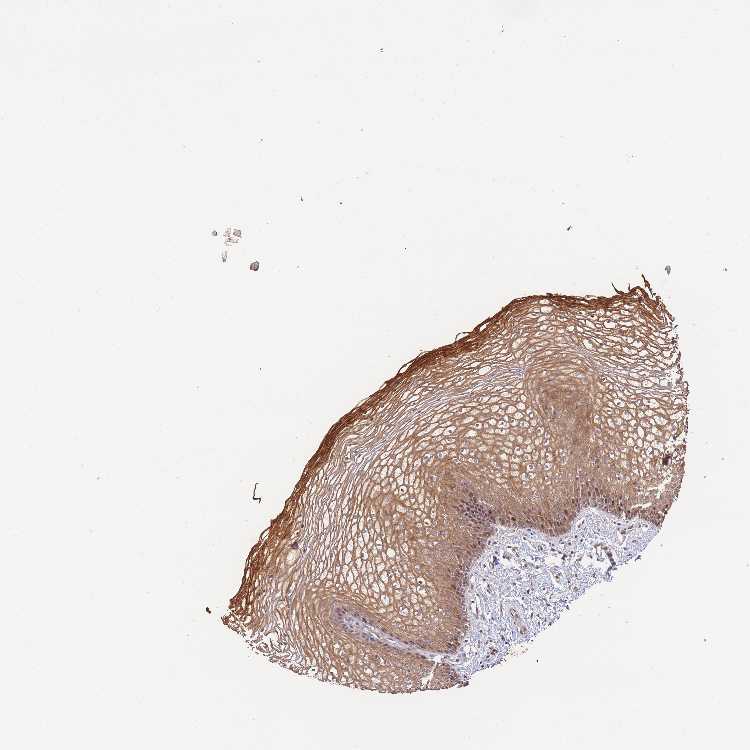

Antibody HPA046847

Squamous epithelial cells Medium